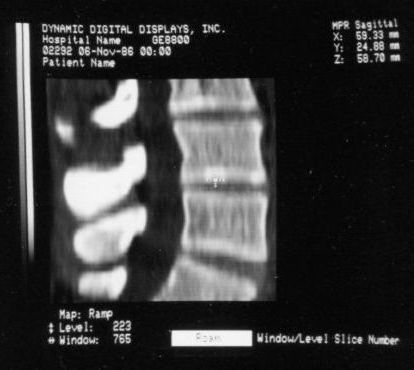

Voxel Processor Prototype Shaded Surface and Multiplanar Reformatteed Images

Since the VPP hardware only generated rendered images from the 64-cube with no annotation, and one image at a time on the video monitor, photos of the monitor must have been scanned into the Jurassic equivalent of Photoshop and combined along with text to create these, or more likely pasted with strips of text onto a black matt and rephotographed. But each one of the little images was rendered in true real-time. ;-)

Voxelscope I Screen Shots. First Row: Multiplanar Reformatting; Second Row: 3-D Shaded Surface

The annotation was generated by the software so no more cutting and pasting. :)

The pair of video monitors was the focus of the booth, displaying sequences of skulls and such from real CT datasets like those in the above photos being rotated, sliced, and diced at reasonably rapid update rates. The instructions for performing the operations were captured and recorded but the actual voxel processing was done in real-time based on the stored program. Thus, no one needed to be constantly spinning the trackball, though that could have been arranged upon request. :) The monitors were up high so visitors couldn't get close enough to see how poor the resolution was. :( :) It is believed that VS1 had a microcode-based pipeline running at 10 MHz so that a 128-cube (2,097,152 voxels) could be manipulated at around 5 images per second. The display was 256x256 pixels on a 60 Hz non-interlaced display - double that of VPP. But object space could be configured to be any arbitrary rectangular prism as long as all the data fit into the voxel processor's memory. The photos, above, are typical of the displays at RSNA.